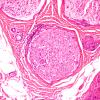

PERIPHERAL NEUROPATHY

15 NEUROPATHY ASSOCIATED WITH NEOPLASIA

2 Paraneoplastic Neuropathy (7)